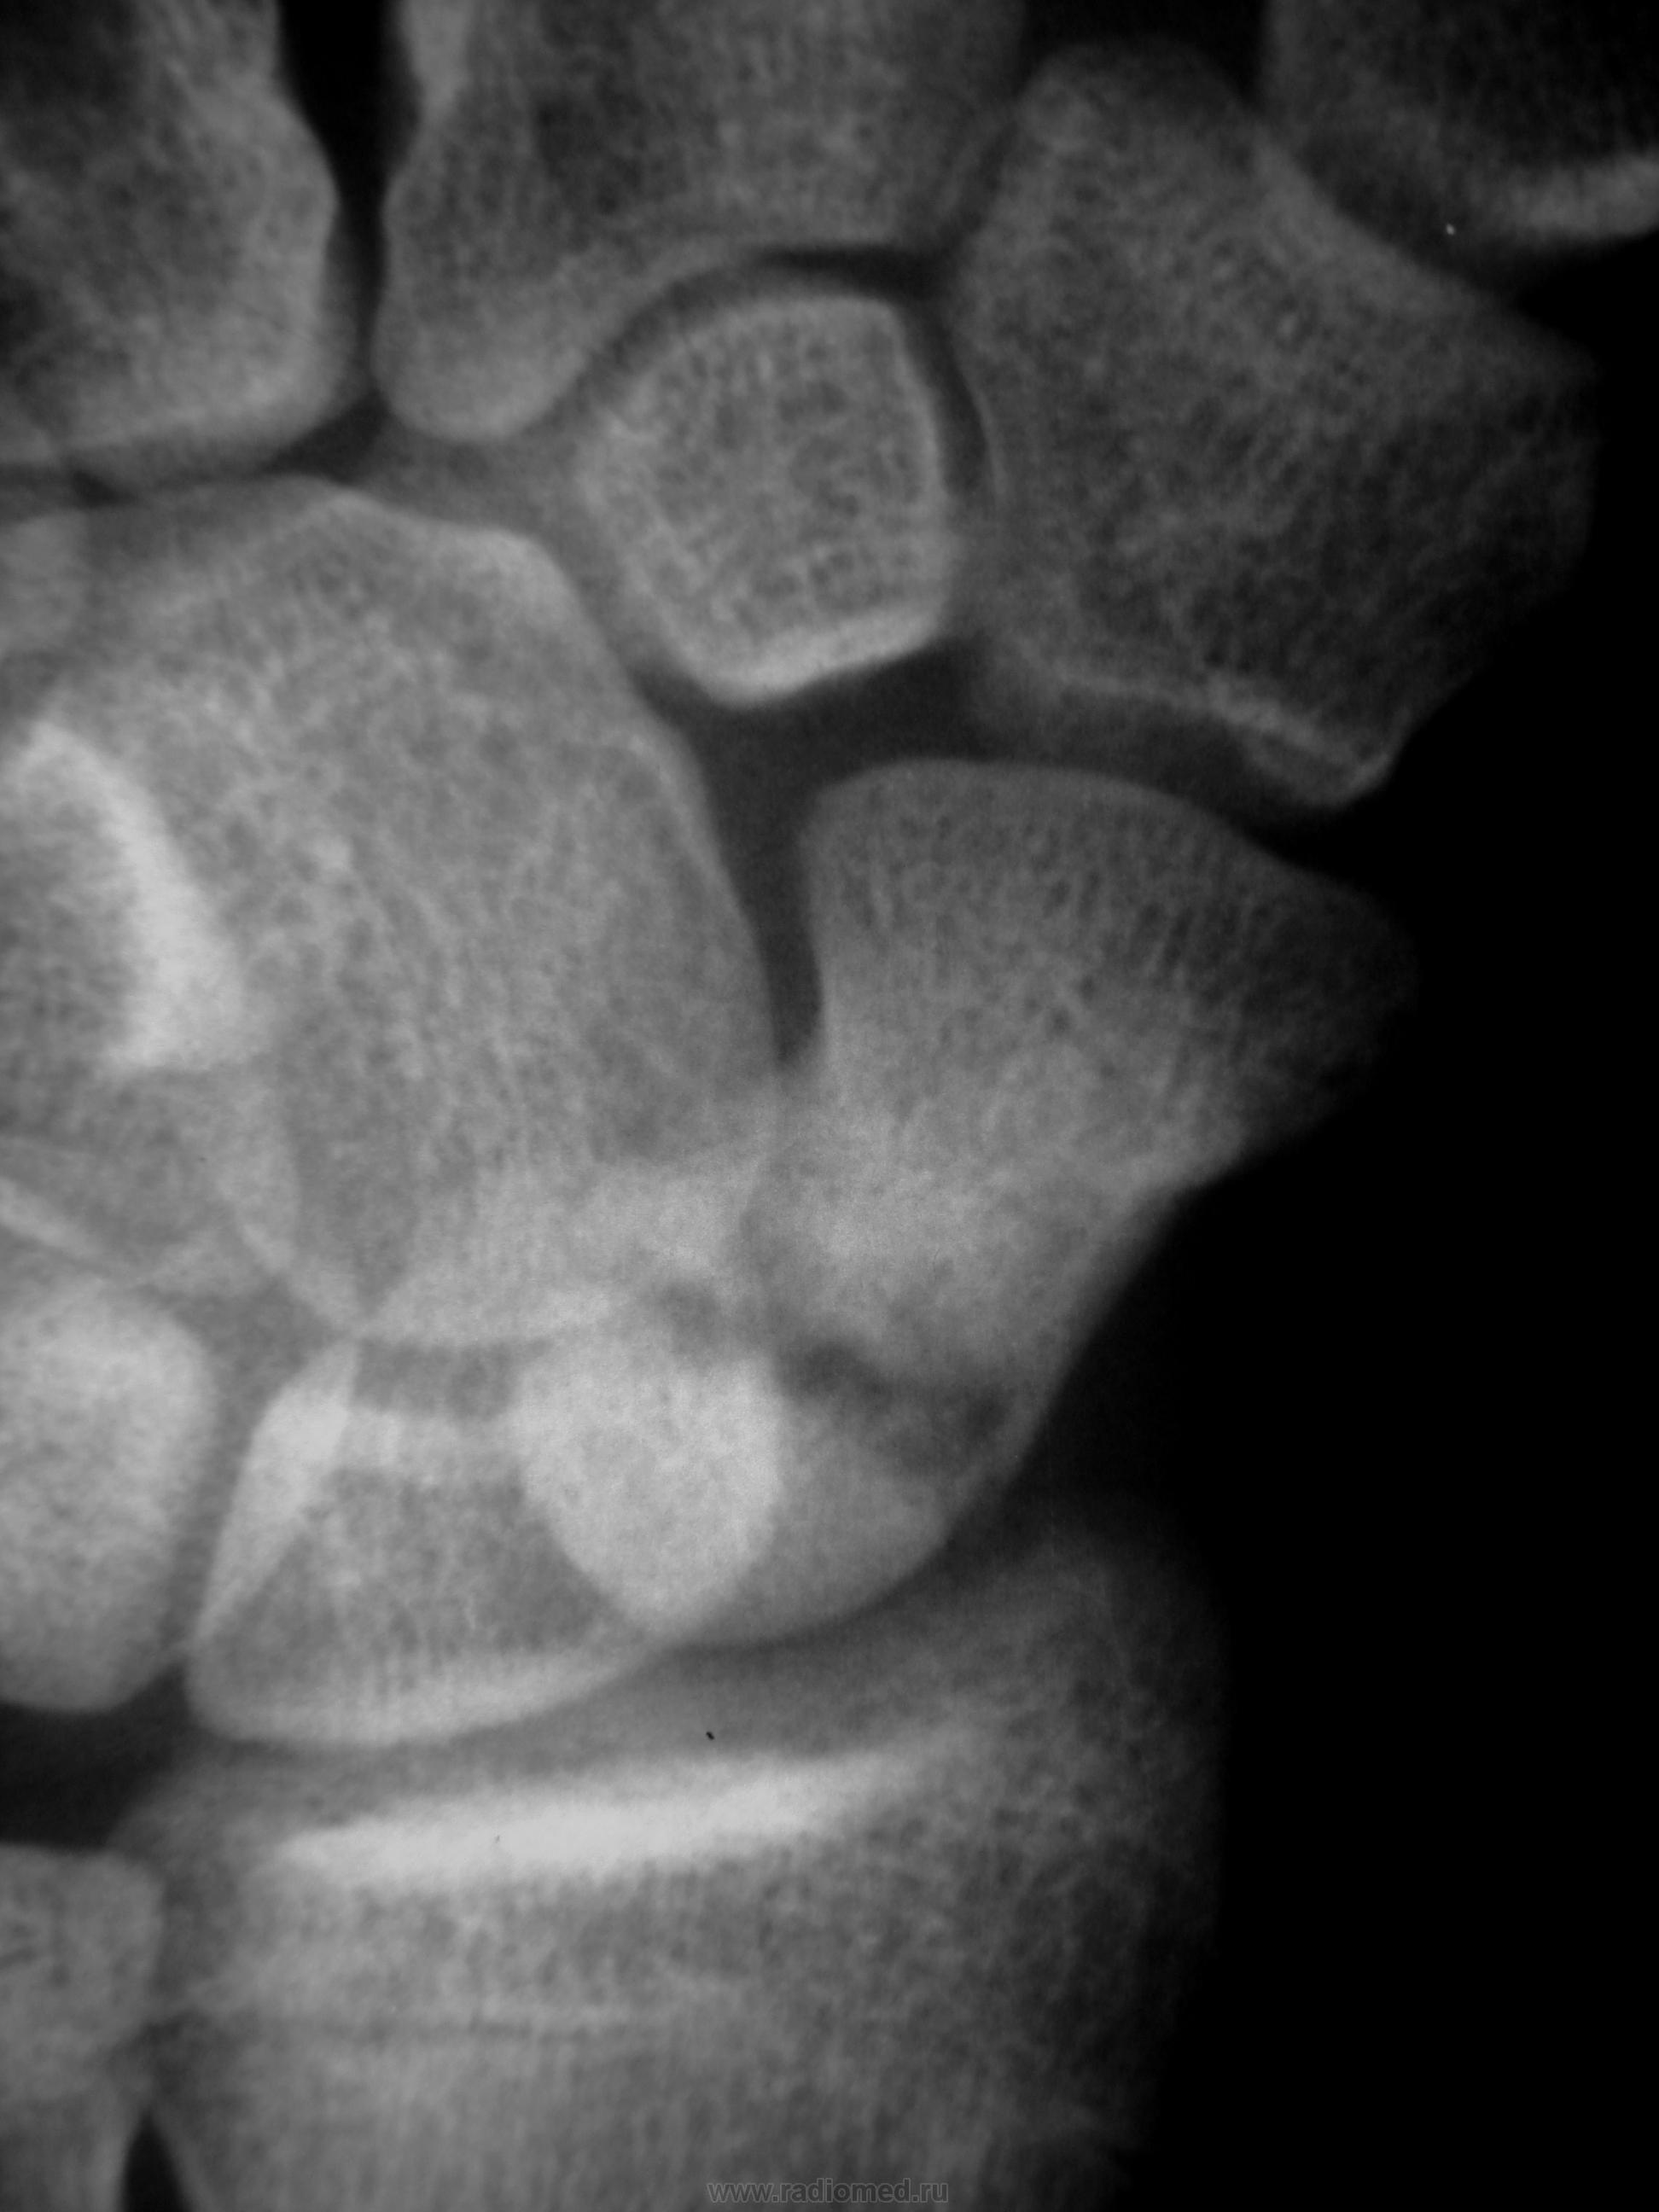

Травма в октябре 2009,сейчас появились боль, припухлость в обл. ладьевидной кости. Какие будут мнения, уважаемые коллеги?

Значит в октябре не болело. Это странно. Несросшийся перелом есть. А вот псевдартроз как-то не очень... Здесь нужна проекция для ладьевидной кости, без наслоений других.

В  октябре само сабой болело,перелом был диагносцирован,ходил в гипсе, но через месяц сняли и носили ортез. Не болело до настоящего времени.

В наших условиях - знатоки говорят о необходимости операции чуть ли не в первые 2 часа после перелома, переломы ладьи никогда не срастаются...